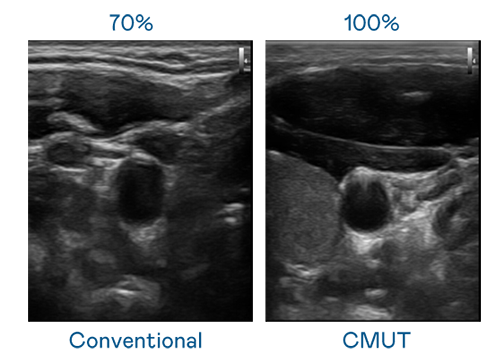

CMUT 技术是一种用电容式微机电元件来产生超音波讯号的技术。与传统 PZT 压电式技术相比,CMUT 频宽增加 30%,更宽频的超音波讯号让影像解析度大幅提升,是实现高影像品质医疗超音波扫描、促进精准医疗发展的关键技术。

大频宽带来超清晰影像超音波影像的解析度高低,首先取决于探头能发出的讯号频宽。果冻传媒原创 CMUT 可提供高清晰的超音波讯号,提供高频宽、高灵敏度、影像纹理细节更高的超音波影像,协助医护人员缩短影像判读时间及利用精准的医疗影像进行诊断。